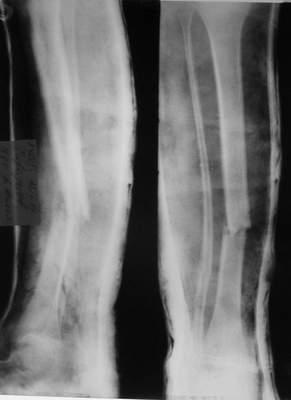

Так как речь зашла непосредственно о травме, см этапные

снимки. Как все было

Первичные

Вытяжение

Фиксация

в гипсе

Промежуточный